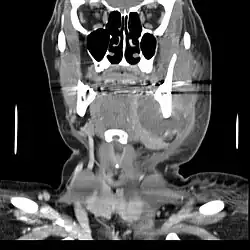

Normalmente, os abscessos dentais não aparecem radiograficamente, mas abscessos de tamanho exuberante ou de longa data podem se apresentar como lesões radiolúcidas de limites mal definidos.[1][3] Na tomografia computadorizada de feixe cônico (TCFC), os abscessos também se apresentam como lesões osteolíticas (hipodensas) em tecidos moles: a TCFC pode ser útil para o diagnóstico diferencial em lesões grandes ou para avaliar o envolvimento dos seios da face, mas não é considerada essencial para o tratamento de abscessos periapicais.[3][5]